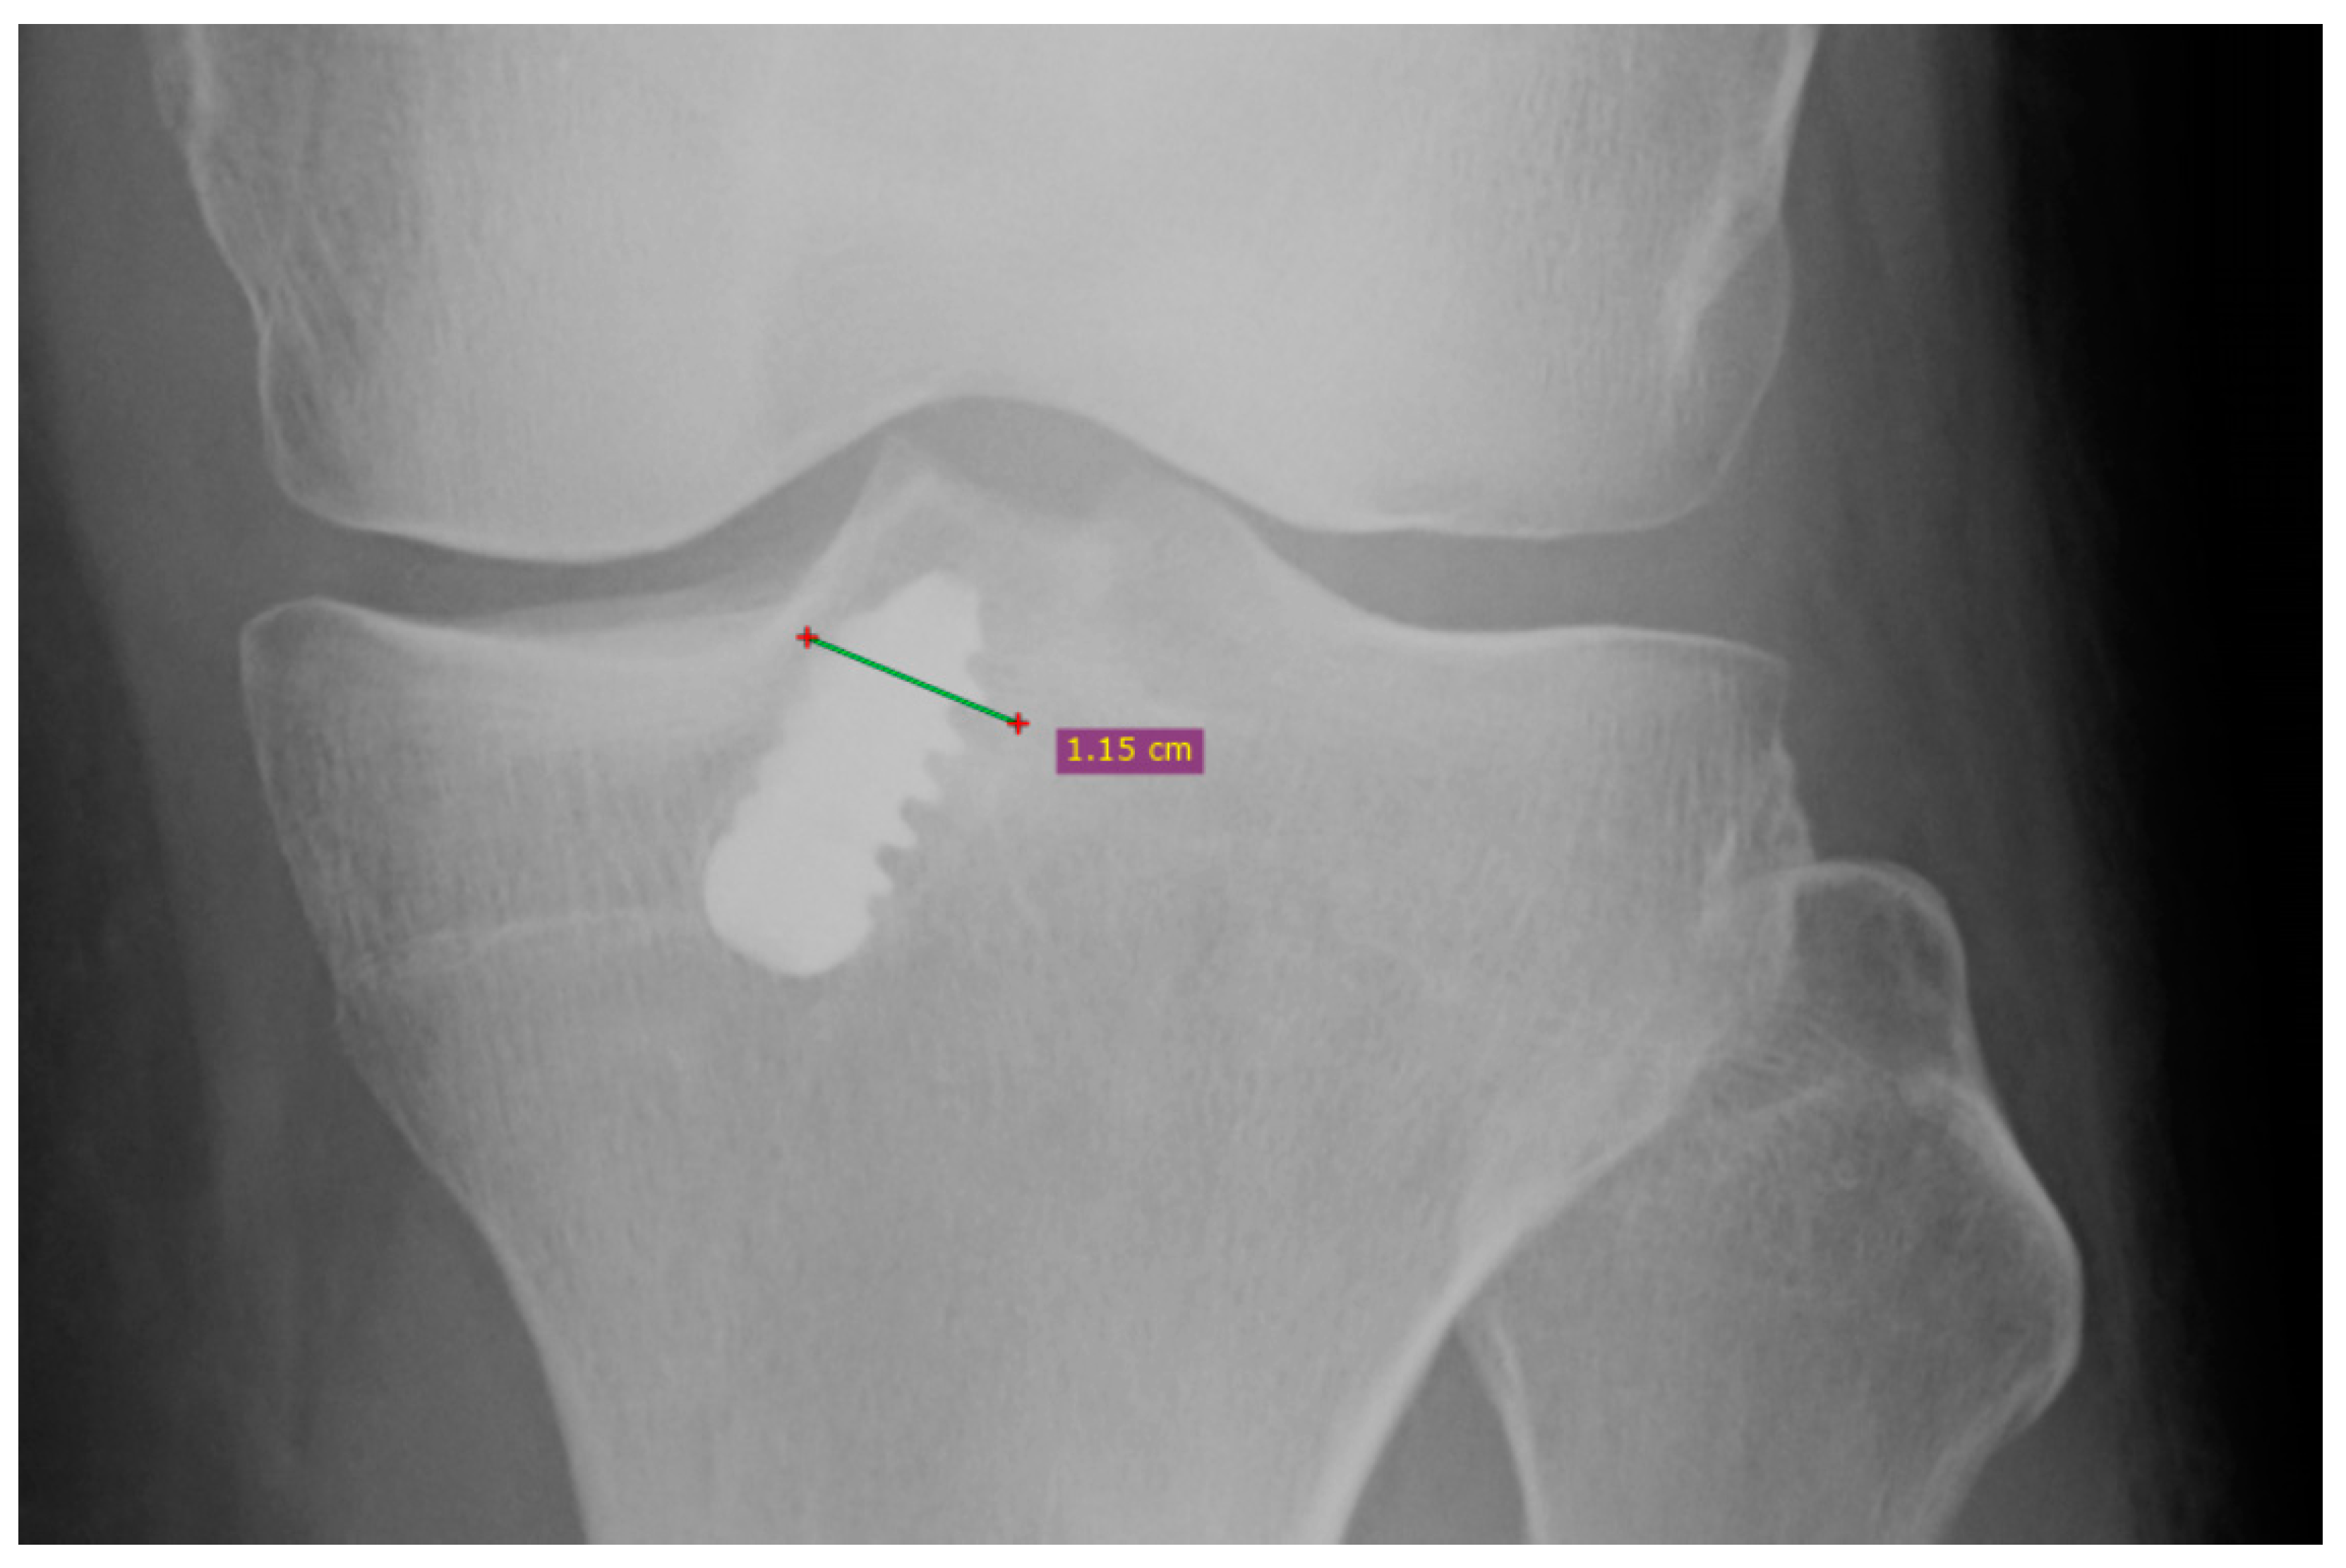

| Presence of tibial widening | 23/54 patients | 28/52 patients | A |

| Mean tibial widening | 1.4 mm | 2.1 mm | NA |